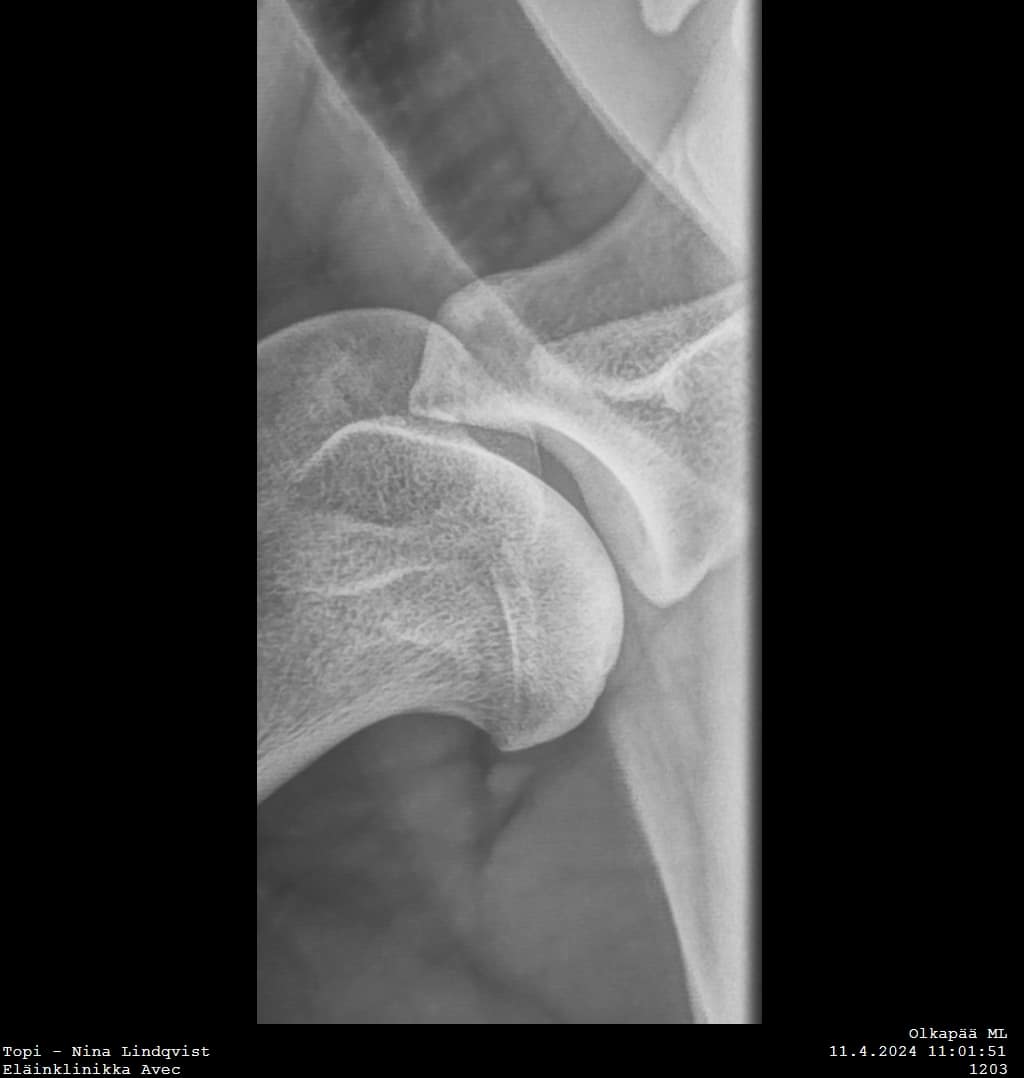

Topilta röntgenkuvattiin olat ja kyynärät. Kyynärissä ei ollut huomauttamista, ja molempien olkien tilanne on olkaluunpään osalta tosi hyvä. Parantuminen on edelleen käynnissä, eikä minkäänlaisia merkkejä nivelrikosta ole. Ja sitten se mutta. Vasemman olan glenoidaalikuopassa näkyy pieni röntgenharva alue. Olkanivelet myös ultrattiin, ei poikkeavia löydöksiä.

On mahdollista että Topilla on nyt sitten osteokondroosi myös tässä lapaluun alaosassa. Asian varmistamiseksi tarvittaisiin jälleen lisätutkimuksia tai jopa uusi tähystysleikkaus. Aiheuttaako tuo glenoidaalikuopas muutos nyt nämä kipuoireet vai ei, kas siinäpä kysymys. Varmaa diagnoosia emme siis tällä käynnillä saaneet.

Tässä on nyt hetki sulateltu uusimpia löydöksiä ja pohdittu jatkoa. Olen saanut näkemyksiä tilanteesta eri ortopedeiltä, ja kyllä ammattilaisten veikkaus on, että Topilla on osteokondroosi myös siellä lapaluun nivelkuopassa. Asian varmistaminen vaatisi jatkotutkimuksia ja niitä vielä pohditaan.